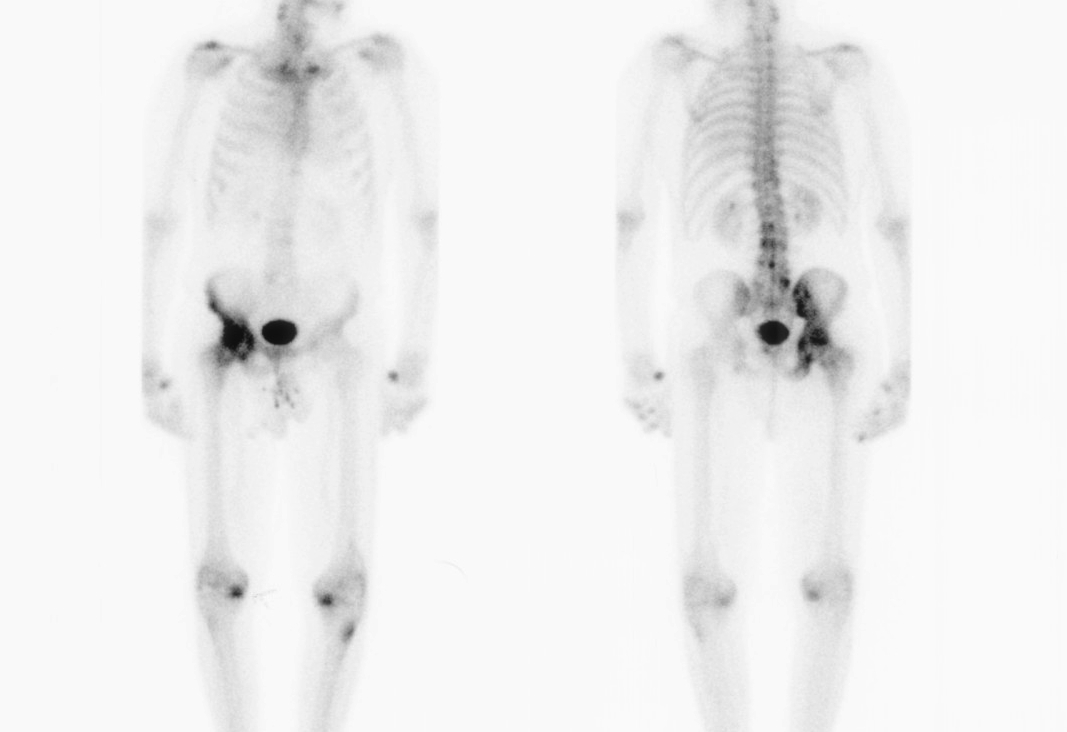

Bone scan

Shows increased uptake / will only detect active disease